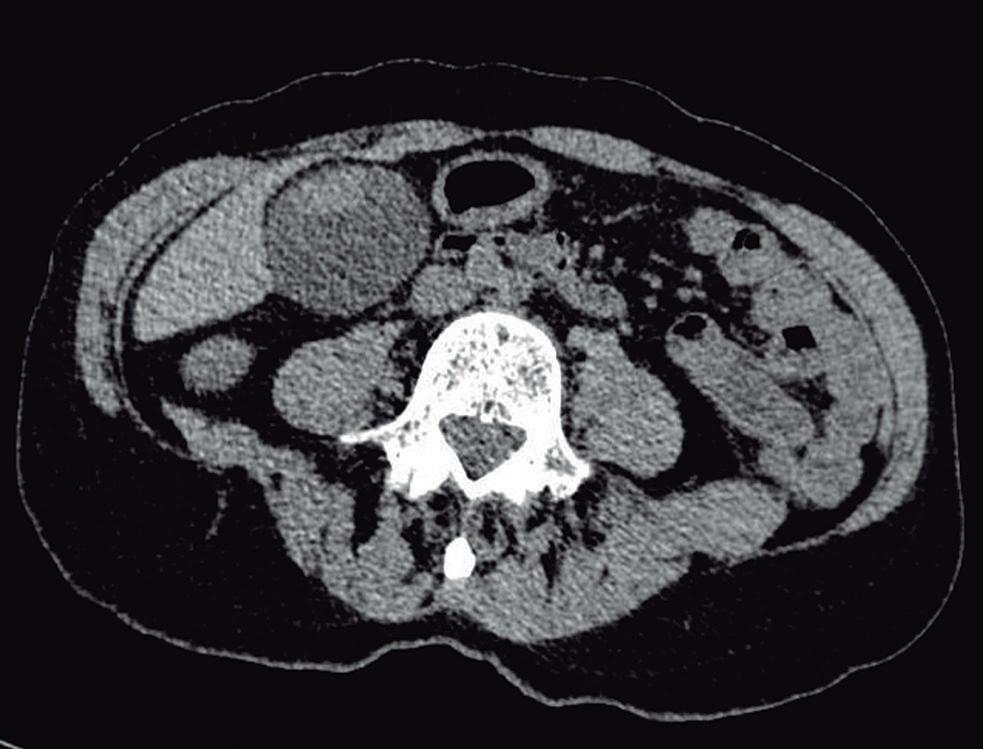

Adenoma hepatocelular

Los AHC son lesiones formadas por hepatocitos normales dispuestos en una histoarquitectura anormal y carecen de conductos biliares funcionales, sistema venoso portal y células de Kupffer. Son lesiones infrecuentes

(10 veces menos que la HNF) que suelen ocurrir en mujeres jóvenes que han recibido anticonceptivos orales (ACO) y en pacientes con obesidad, síndrome metabólico y diabetes. También ocurren en pacientes con enfermedad por depósito de Glucógeno tipo 1 (Von Gierke).

Debido a que conllevan riesgo variable de malignidad así como también de sangrado espontáneo y rotura con volcado peritoneal, su diagnóstico certero es fundamental para determinar el manejo ulterior. En el año 2006 se estableció una clasificación en subtipos basada en características genéticas, moleculares e histológicas. 9 Dichos subtipos incluyen: AHCI (30-40%), AHC asociado a inactivación de oncogén del factor nuclear hepatocitario α 1 (30-35%), asociado a mutación β -catenina (10-20 %) e inclasificados. Esta última representa una categoría de exclusión. Posteriormente se describieron tres variantes adicionales: la variedad AHC con activación de la vía sonic Hedge y ACH combinados que incluyen AHCI asociado a mutación beta catenina exón 3 y AHCI asociado a mutación beta catenina exón 7/8. 10

Los AHC suelen tener un aspecto similar a la HNF en las imágenes (textura similar al parénquima hepático normal e hipervascular) pero con algunas diferencias de acuerdo al subtipo que permiten la diferenciación con frecuencia, en particular, mediante la RM.

Adenoma hepatocelular inflamatorio

El AHCI es el tipo más frecuente y se asocia al uso de ACO y también en mujeres jóvenes con obesidad, diabetes y síndrome de inflamación sistémica. Histológicamente se destaca la vascularización con sinusoides dilatados, la peliosis y la presencia de inflamación. Debido a que la red vascular débil está expuesta al flujo aumentado por ramas arteriales hipertróficas tiene mayor riesgo de sangrado. Se ha establecido como valor de corte para la intervención 5 cm. Dicho valor está basado en el mayor riesgo de sangrado en las lesiones más voluminosas.

En la RM tiene tipicamente una señal hiperintensa en secuencia T2 debido a su vascularización e inflamación, (Figura 6) a menudo con un halo periférico de alta señal conocido como signo del atolón (presuntamente por sinusoides dilatados). Tras la administracion de contraste exhiben hiperrefuerzo en fase arterial con disipación posterior del contraste, es decir, haciéndose frecuentemente isointensos en fase venosa portal o de equilibrio y sin lavado (wash-out).1

Esta última es una característica clave para diferenciarlo del CHC en hígado no cirrótico. Al igual que el CHC puede presentar una cápsula más evidente en imágenes tardías.

El AHCI carece en general de transportadores OATP y de ductos biliares funcionales por lo que típicamente, no refuerza con el CHE en fase hepatobiliar.12

Debido a la asociación con dismetabolismo, el AHCI se observa frecuentemente en hígados con esteatosis, un motivo más que jerarquiza el empleo de la RM en lugar de la TC ya que el depósito graso subyacente suele enmascarar lesiones en esta última técnica.

Lesiones benignas localizadas en el hígado desde la mirada de las imágenes Mariano Volpacchio Figura 6. Adenoma hepatocelular inflamatorio A: Imagen axial ponderada en secuencia T2 que demuestra una pequeña lesión nodular moderadamente hiperintensa en el segmento V. B: Imagen ponderada en secuencia T1 en fase arterial que demuestra el hiperrefuerzo de la lesión relativamente homogéneo. C: En secuencia T1 obtenida en fase posterior se disipa el refuerzo y sólo persiste una sutil zona de mayor intensidad. A